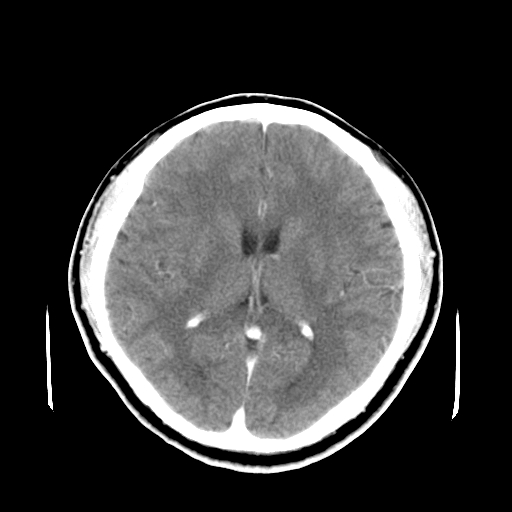

标题: CT16447B:(续)增强扫描图像。

患者今日做ct增强检查,现补传增强扫描图像。

松果体钙癍增大,无其他改变,定不了性

一般认为大于1cm为异常。